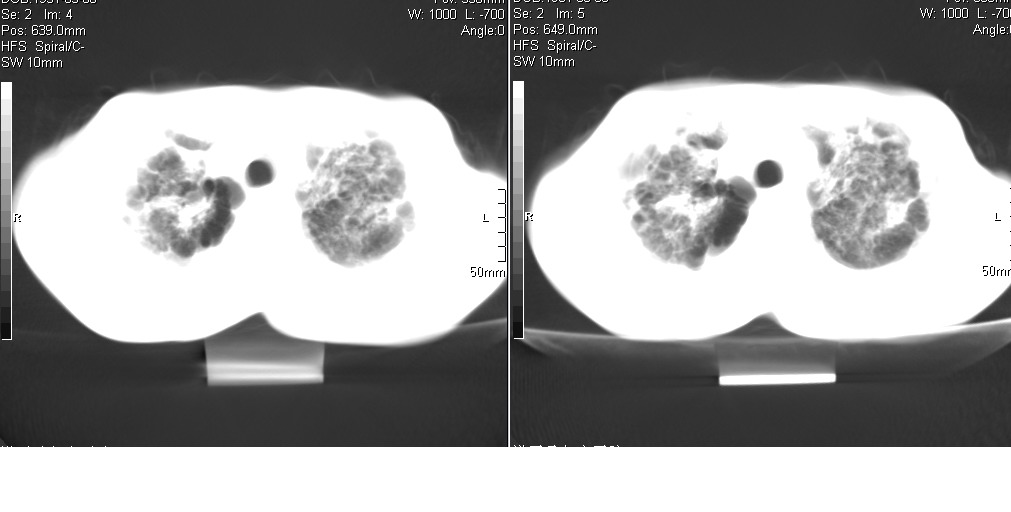

以下是引用光线在2008-5-6 18:36:00的发言:[br]双肺结核(左上肺空洞形成)、间质性改变合并感染,右肺大泡;右侧胸膜增厚。

以下是引用zsl6918在2008-5-7 1:54:00的发言:[br]首先肺泡蛋白质沉着症,其次考虑机遇性感染。